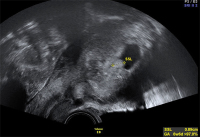

Tipps und Tricks im Gyn-Ultraschall: Die Sectionarbe am nichtschwangeren Uterus und in der Frühschwangerschaft

Journal für Gynäkologische Endokrinologie 2014; 8 (2) (Ausgabe für Österreich): 22-24 Journal für Gynäkologische Endokrinologie 2014; 8 (2) (Ausgabe für Schweiz): 24-26 Volltext (PDF) Abbildungen